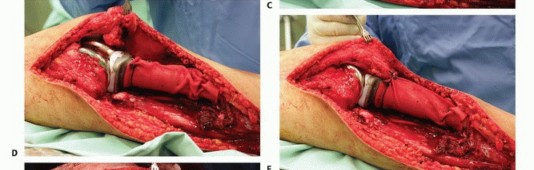

دور سديلة العضلة التوأمية الإنسية (Gastrocnemius Rotational Flap)

يُعد استخدام سديلة العضلة التوأمية الإنسية (عضلة الساق) عاملاً رئيسياً في تحقيق تغطية كافية للأنسجة الرخوة للطرف الصناعي واستعادة وظيفة آلية المد. تُنقل هذه العضلة لتدور إلى الأمام لتغطية الطرف الصناعي، مما يقلل بشكل كبير من خطر العدوى ومضاعفات الجروح، وهو ما كان يمثل تحدياً كبيراً في الماضي. يؤكد الأستاذ الدكتور محمد هطيف على أن هذه التقنية أصبحت إجراءً روتينياً وموثوقاً لضمان تغطية الطرف الصناعي وتقليل معدل العدوى ونخر السديلة والبتر الثانوي.

تفاصيل الإجراء الجراحي للحفاظ على الطرف

تُعد جراحة الحفاظ على الطرف في أورام قصبة الساق القريبة إجراءً معقداً يتطلب خبرة جراحية عالية وتخطيطاً دقيقاً. يقوم الأستاذ الدكتور محمد هطيف بتطبيق أحدث التقنيات لضمان استئصال الورم بشكل كامل وإعادة بناء الطرف بأمان وفعالية. تتضمن الجراحة ثلاث خطوات رئيسية:

- استئصال الورم: إزالة الجزء المصاب من قصبة الساق والأنسجة المحيطة به مع هامش أمان كافٍ.

- إعادة بناء العيب الهيكلي ومفصل الركبة: زرع طرف صناعي أو طعم عظمي لاستبدال الجزء المستأصل.

- إعادة بناء آلية المد وتغطية الطرف الصناعي بالأنسجة الرخوة: استخدام سديلة العضلة التوأمية لضمان التغطية والحفاظ على وظيفة الركبة.

تقنيات الجراحة المتقدمة

التعرض الجراحي

يتم إجراء شق واحد أمامي إنسي، يبدأ من الثلث البعيد لعظم الفخذ ويستمر إلى الثلث البعيد لقصبة الساق. يشمل هذا الشق استئصال موقع الخزعة، والذي يظل متصلاً بالعظم الأساسي لضمان إزالة جميع الخلايا السرطانية المحتملة. يتم تطوير سدائل سميكة من الجلد والأنسجة تحت الجلد، بما في ذلك اللفافة، لتقليل احتمالية نقص تروية السديلة.

استكشاف الحفرة المأبضية والحزمة الوعائية

يجب استكشاف تفرع الشريان المأبضي مبكراً لتحديد ما إذا كان الورم قابلاً للجراحة، خاصة إذا كانت مكوناته في الأنسجة الرخوة تمتد خلفياً. إذا لم يكن هناك امتداد خلفي، يتم تعريض الفراغ المأبضي والتفرع عن طريق فصل العضلة التوأمية الإنسية وشق العضلة النعلية. يمكن تحديد الشريان المأبضي بسهولة وتتبعه بعيداً حول العضلة المأبضية. يجب توخي الحذر لتحديد وحماية جميع الفروع الوعائية الرئيسية.